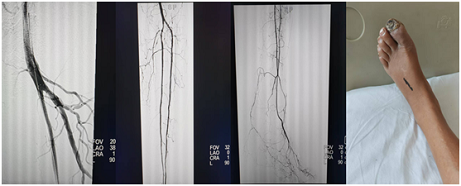

患者左足缺血症状明显,CTA示下肢动脉长段闭塞

微信图片_20250225185417

术前基线造影示多处长段病变